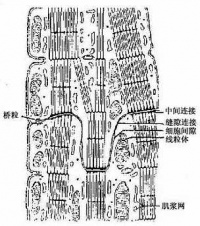

心肌细胞与骨骼肌的结构基本相似,也有横纹,但在结构上具有以下几个特征:

①心肌细胞为短柱状,一般只有一个细胞核,而骨骼肌纤维是多核细胞。心肌细胞之间有闰盘结构。该处细胞膜凹凸相嵌,并特殊分化形成桥粒,彼此紧密连接,但心肌细胞之间并无原生质的连续。心肌组织过去曾被误认为是合胞体,电子显微镜的研究发现心肌细胞间有明显的隔膜,从而得到纠正。心肌的闰盘有利于细胞间的兴奋传递。这一方面由于该处结构对电流的阻抗较低,兴奋波易于通过;另方面又因该处呈间隙连接,内有15~20埃的嗜水小管,可允许钙离子等离子通透转运。因此,正常的心房肌或心室肌细胞虽然彼此分开,但几乎同时兴奋而作同步收缩,大大提高了心肌收缩的效能,功能上体现了合胞体的特性,故常有“功能合胞体”之称。

②心肌细胞的细胞核多位于细胞中部,形状似椭圆或似长方形,其长轴与肌原纤维的方向一致。肌原纤维绕核而行,核的两端富有肌浆,其中含有丰富的糖原颗粒和线粒体,以适应心肌持续性节律收缩活动的需要。从横断面来看,心肌细胞的直径比骨骼肌小,前者约为15微米,而后者则为100微米左右。从纵断面来看,心肌细胞的肌节长度也比骨骼肌的肌节为短。

③在电子显微镜下观察,也可看到心肌细胞的肌原纤维、横小管、肌质网、线粒体、糖原、脂肪等超微结构。但是心肌细胞与骨骼肌有所不同;心肌细胞的肌原纤维粗细差别很大,介于0.2~2.3微米间;同时,粗的肌原纤维与细的肌原纤维可相互移行,相邻者又彼此接近以致分界不清。心肌细胞的横小管位于Z线水平,多种哺乳动物均有纵轴向伸出,管径约0.2微米。而骨骼肌的横小管位于A-I带交界处,无纵轴向伸出,管径较大,约0.4微米。心肌细胞的肌质网丛状居中间,侧终池不多,与横小管不广泛相贴。总之,心肌细胞与骨骼肌细胞在形态和功能上均各有其特点。